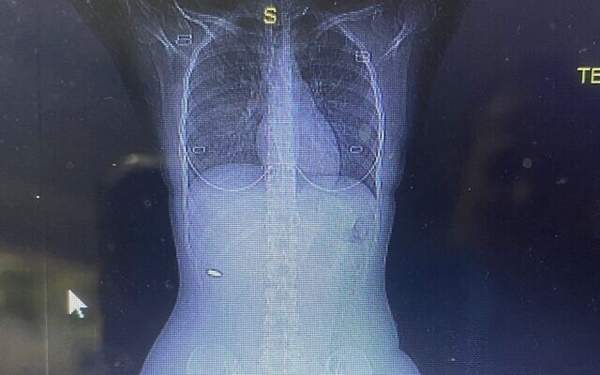

3 tháng sau đám cưới, cô Bloy vẫn chịu cơn đau nhức dai dẳng nên đã quyết định tới bệnh viện để kiểm tra. Cô yêu cầu chụp ảnh cắt lớp vi tính (CT), cho thấy có vật thể dạng kim loại gần cột sống. Sau khi tiến hành phẫu thuật gắp dị vật, các bác sĩ nhận ra đó là một viên đạn cỡ 5,56mm, chuyên dùng cho súng trường.